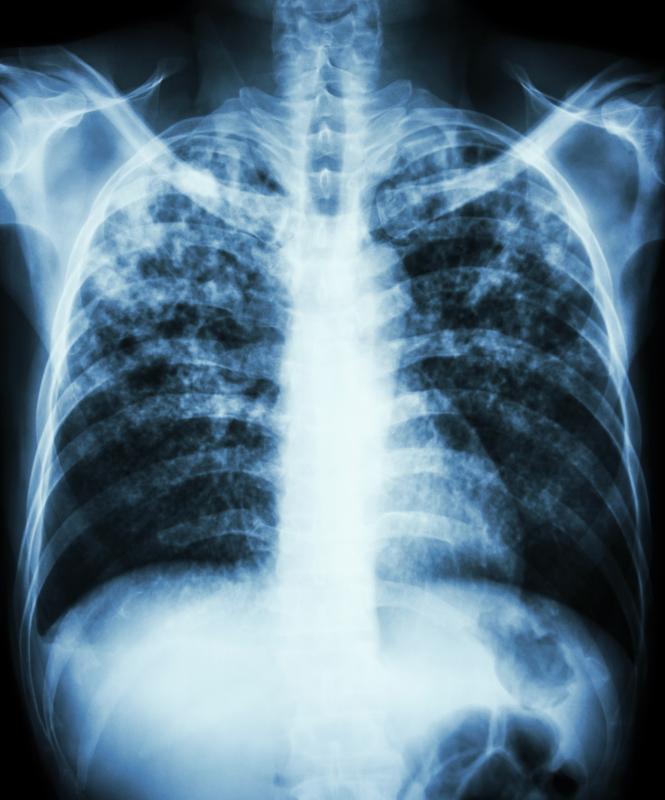

Adolescents with tuberculosis (TB), especially those aged >15 years, may develop symptoms and conditions akin to those seen in adults with TB, suggests a study. In addition, there appears to be an increased incidence of severe pulmonary disease leading to pulmonary sequelae.

Adolescents aged >15 years were more likely to have lung imaging findings consistent with severe disease. Respiratory cultures turned out positive in most of the obtained samples (62 percent).

In addition, “[p]ulmonary cavities and positive bacilloscopy were associated with the presence of pulmonary sequelae at the end of treatment,” the investigators said.